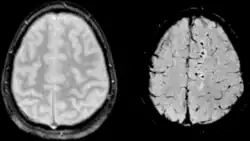

| Two MRI images of a patient with diffuse axonal injury resulting from trauma, at 1.5 tesla field strength. Left: conventional gradient recalled echo (GRE). Right: Susceptibility weighted image (SWI). | |